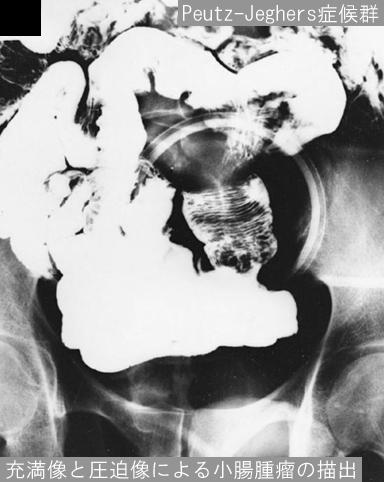

Posted by: Tokyo Pref., 国立癌中心中央病院和九州癌中心共同完成